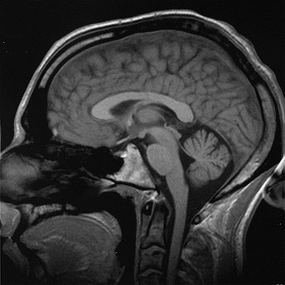

(Courtesy of Wikimedia Commons and Christian R. Linder)

This COBRE grant is only part of the university's plan to expand its neuroscience program. The university plans to hire more professors with research expertise in cognitive neuroscience and MRI technology. UNR intends to spend nearly half a million dollars purchasing two new neuro-imaging systems, as well as creating an on campus MRI facility staffed by a new faculty member.

Professor Marion Berryhill’s laboratory is exploring how brain lesions affect cognition and memory, techniques to improve human memories, and the nature of internal attention. In her research she uses neuropsychological (patient-based), neuroimaging (MRI) and neurostimulation to understand the inner working of the brain. Her laboratory is currently using electrical stimulation to the brain as a technique to improve mental ability during memory tests. All of these projects are aimed at helping us to understand the nature of memory as well as how to maintain our memory as we age. |

The laboratory of professor Xiaoshan Zhu is developing new nanoparticles that are able to detect extremely low levels of biomarkers, such conditions as: cancer, infectious diseases, and neural diseases. These nanoparticle have a very small volume in comparison to their surface area, and are engineered with unique properties. These properties allow them to target specific humans locations in the human body from proteins to tissue. The presence of these particles lets MRI create clearer picture with more contrast. With the help of these engineered nanoparticles, we will be able to see brain damage and help fix it. |